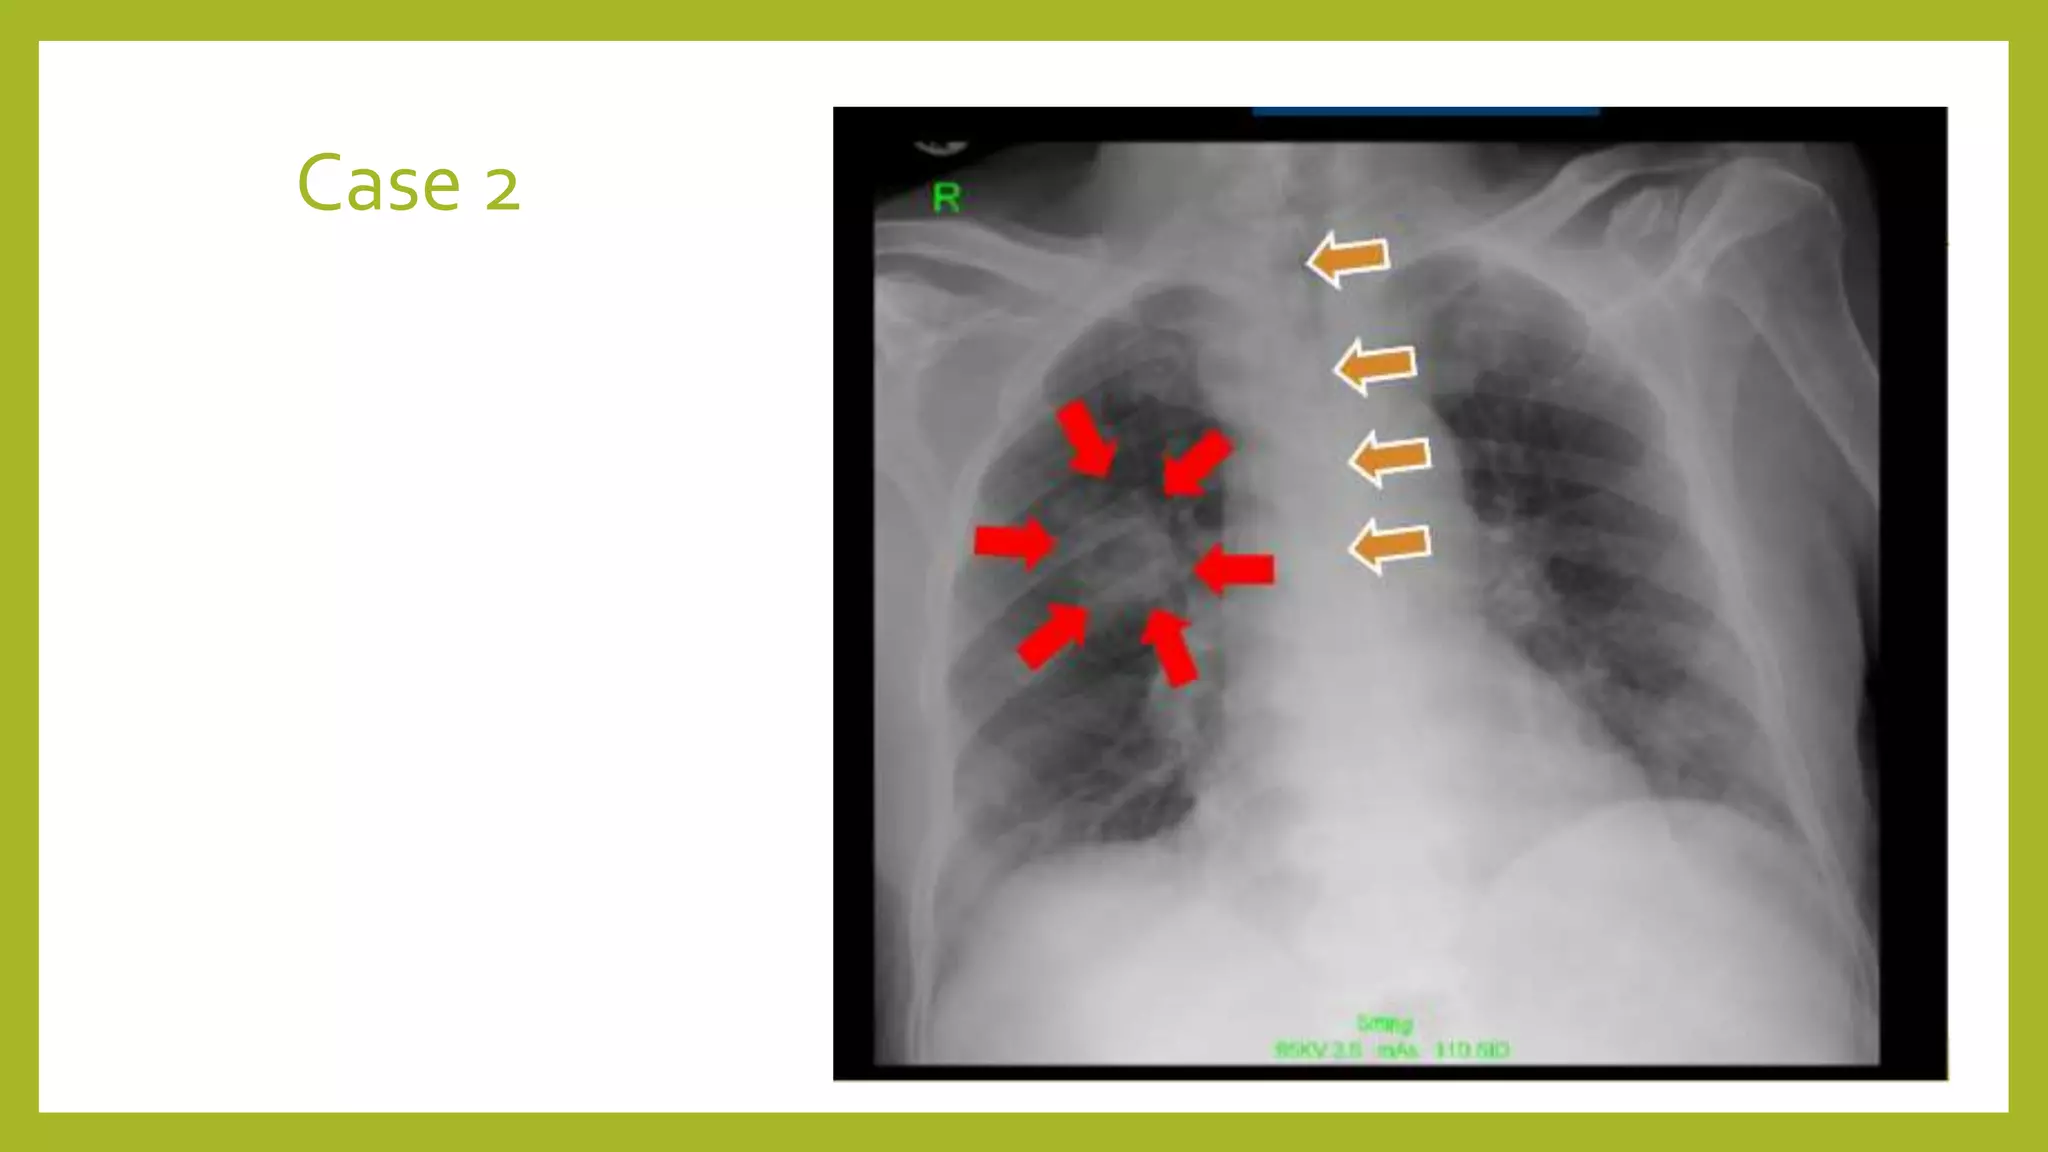

The document provides guidance on approaching and interpreting chest x-rays (CXR). It outlines steps to check the name, date and quality of the film, systematically scan the CXR looking for abnormalities, and determine if the lungs appear too white or black. Specific signs are described to help localize abnormalities, including the cardiac silhouette sign and pleural effusion signs. Examples are given of respiratory distress syndrome, tetralogy of fallot, transposition of great arteries, and total anomalous pulmonary venous return. The take home message is to summarize positive findings, compare to prior CXRs if available, and confirm findings with a radiologist.